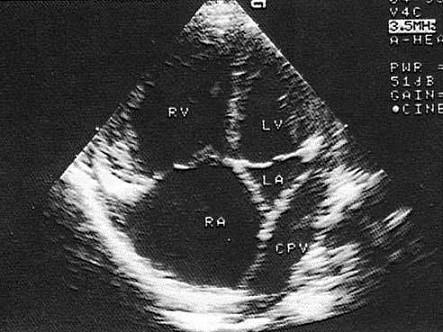

该病例最可能的诊断?(?)A.三房心B.部分性肺静脉畸形引流C.完全性肺静脉畸形引流D.瓣上环E.部分型心内膜垫缺损

问题 该病例最可能的诊断?(?)

选项 A.三房心 B.部分性肺静脉畸形引流 C.完全性肺静脉畸形引流 D.瓣上环 E.部分型心内膜垫缺损

答案 C